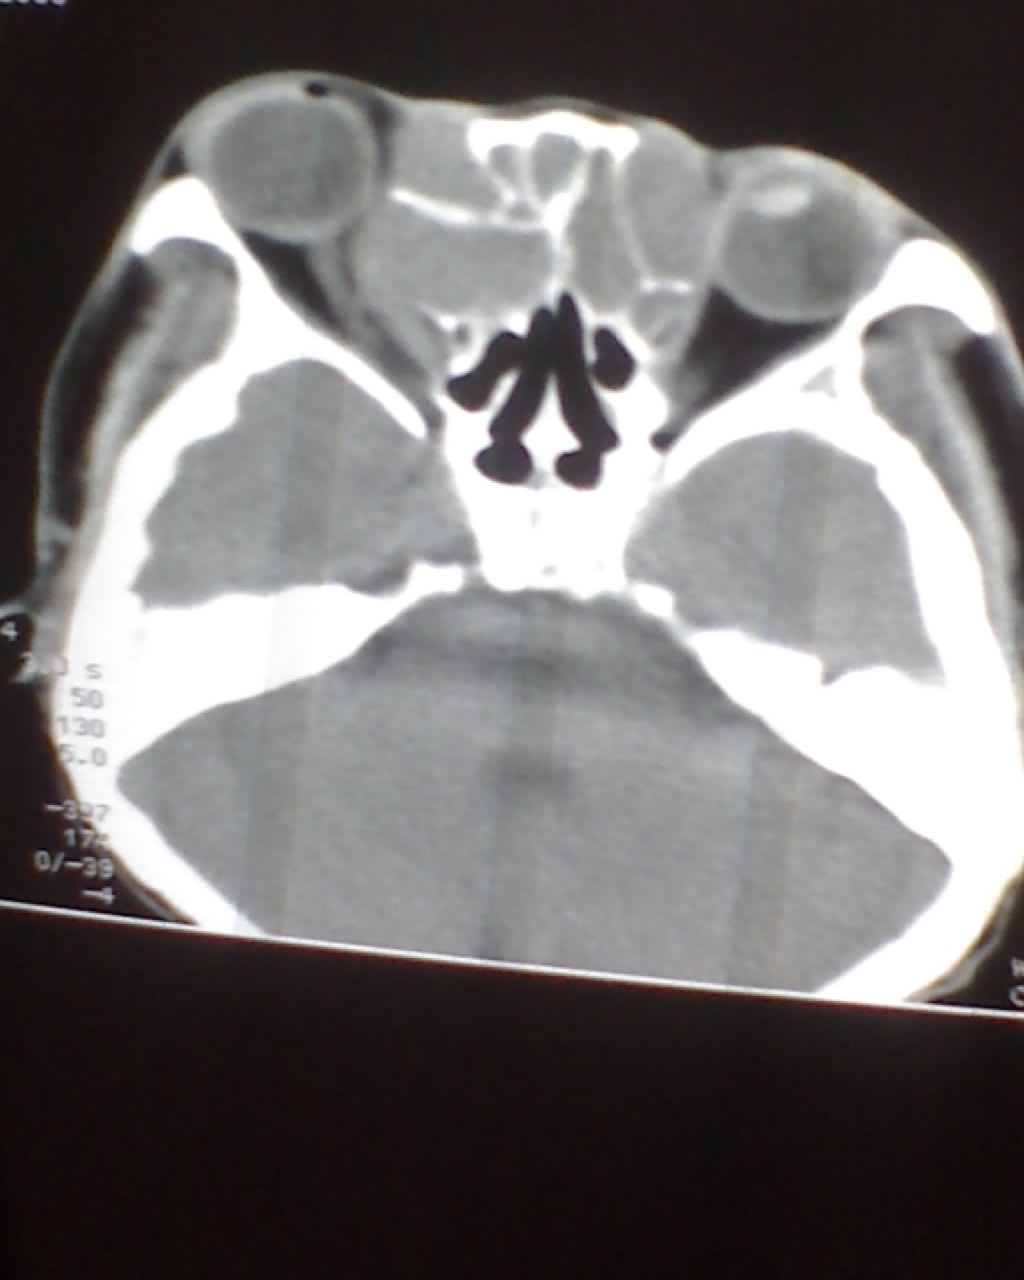

女,45岁,右眼突出,视力模糊来诊。

双侧筛窦可见软组织影充填,筛板破坏,肿块突向双侧眼眶内,以右侧为明显,右侧眼球向前外推压,右视神经稍外移。

考虑良性病变,内翻乳头状瘤可能性大,不除外息肉等。

考虑良性病变,内翻乳头状瘤可能性大,不除外息肉等。支持!(病灶明显起源于鼻窦,呈膨胀性生长,周边骨质吸收 破坏)。

双侧额窦,筛窦可见软组织影充填,筛板破坏,肿块突向双侧眼眶内,以右侧为明显,右侧眼球向前外推压,右视神经稍外移。

考虑良性病变,黏液囊肿可能性大,不除外内翻乳头状瘤等,建议强化.前者不增强.